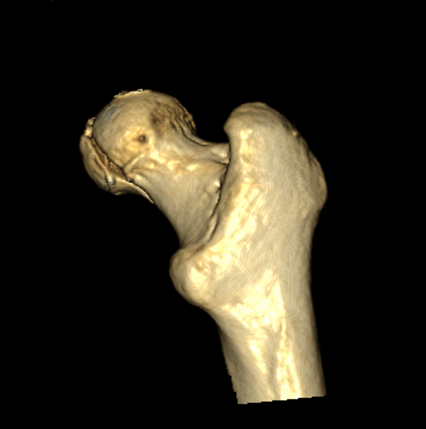

>> За праздники поступил еще один Pipkin IV. Женщина 30 лет, пострадала в

>> ДТП (пассажир). Сочетанная травма (ISS 25). Множественные переломы ребер с

>> двух сторон с пневмотораксом  и пневмомедиастинумом. Закрытый перелом

>> пилона справа. Задний переломо-вывих головки правой бедренной кости (Pipkin

>> IV). Ожирение III- IV  степени. Пацинентка в реанимации, состояние остается

>> тяжелым.

>> довольно сносную картину результата репозиции. Отломок головки оставался в

>> полости сустава во время вывиха, т.к. видимо сохранилось прикрепление со

>> связкой.  На КТ остается широкой суставная щель, что косвенно может

>> указывать на интерпозицию мягкими тканями, либо "встать на место" мешает

>> медиальный отломок головки.